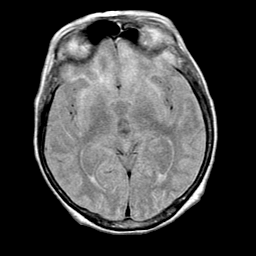

Pick's Disease, MR Study mr-pd -- Slice #10

[Home][Help][Clinical] Slice 10